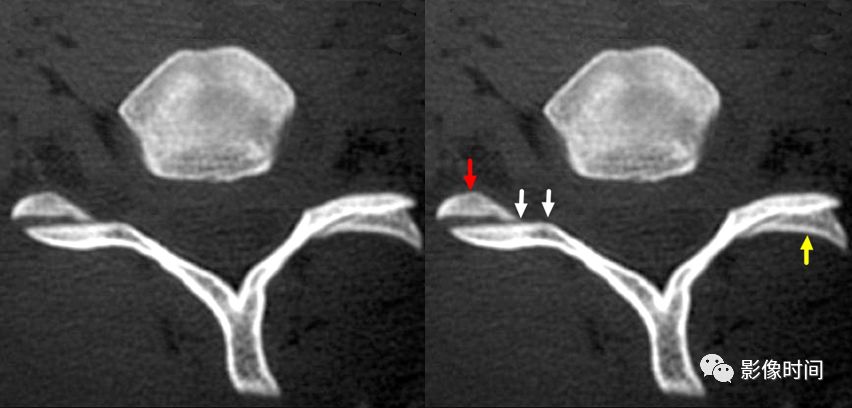

1汉堡包征(脊椎小关节)

本征为颈椎小关节 CT 轴面图像正常的表现。

正常的椎小关节形似汉堡包,椎体上关节突为上部半圆形的小面包样影(黄箭),下关节突位于下部,形成「肉馅」下部的小面包样影(红箭)。小关节突之间的间隙为所谓的「夹馅」(白箭)

认识这一征象,对于小关节脱位和半脱位(A)、退行性改变(B)的诊断有帮助。颈椎 CT 轴面图像:A. 左侧小关节脱位,可见裸面征;右侧小关节半脱位;B. 颈椎小关节退行性变,骨质增生,明显变形,以左侧显著。

2裸面征

裸面征(naked facet sign),又称反汉堡面包征(reverse hamburger bun sign)

当脊椎小关节脱位时,上关节突脱位可位于上关节突后方,关节面向下显露,表现为关节面裸露,为裸面征(黄箭)。脱位可单侧或双侧出现;本例为左侧脱位,右侧为半脱位:可见上关节突(红箭)外移,相对下关节面显露,表现为关节面部分裸露(白箭之间)。

这是屈曲分离型损伤的特点,提示有严重的韧带损伤和脊柱不稳。

上图为 45 岁男性,交通事故后行轴位 CT 检查。显示右侧颈椎汉堡包征异常。双侧关节突不同程度分离、移位。

正常汉堡包征的小关节(下图);外伤后,CT 骨窗示其前部「面包」(上关节突,黑箭)后移,位于下部「面包」(下关节突,白箭)的后方,关节面裸露。